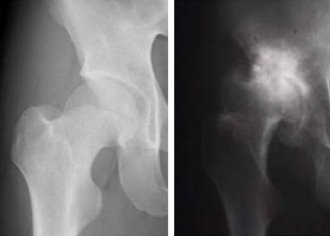

Figure 1: X-rays of a normal hip joint (left) and one affected by osteoarthritis (right).

Led by Shiro Ikegawa at the SNP Research Center of RIKEN in Yokohama, the team analyzed published studies that showed inconsistent results on the importance of one particular gene in the susceptibility to osteoarthritis (OA) (Fig. 1). The gene in question codes for a protein called asporin, which accumulates in arthritic joints.